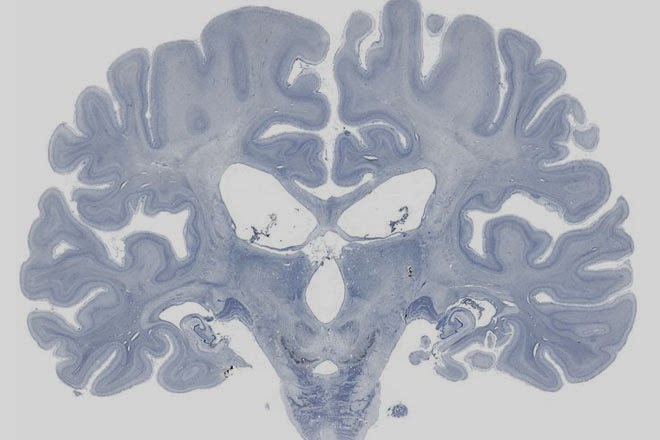

A su muerte, en el año 2008, su cerebro fue preservado por el “Observatorio del Cerebro” quedando a disposición de toda la comunidad cientÃfica y permitiendo a los investigadores seguir aportando datos a uno de los casos más interesantes y estudiados de la neuropsicologÃa.